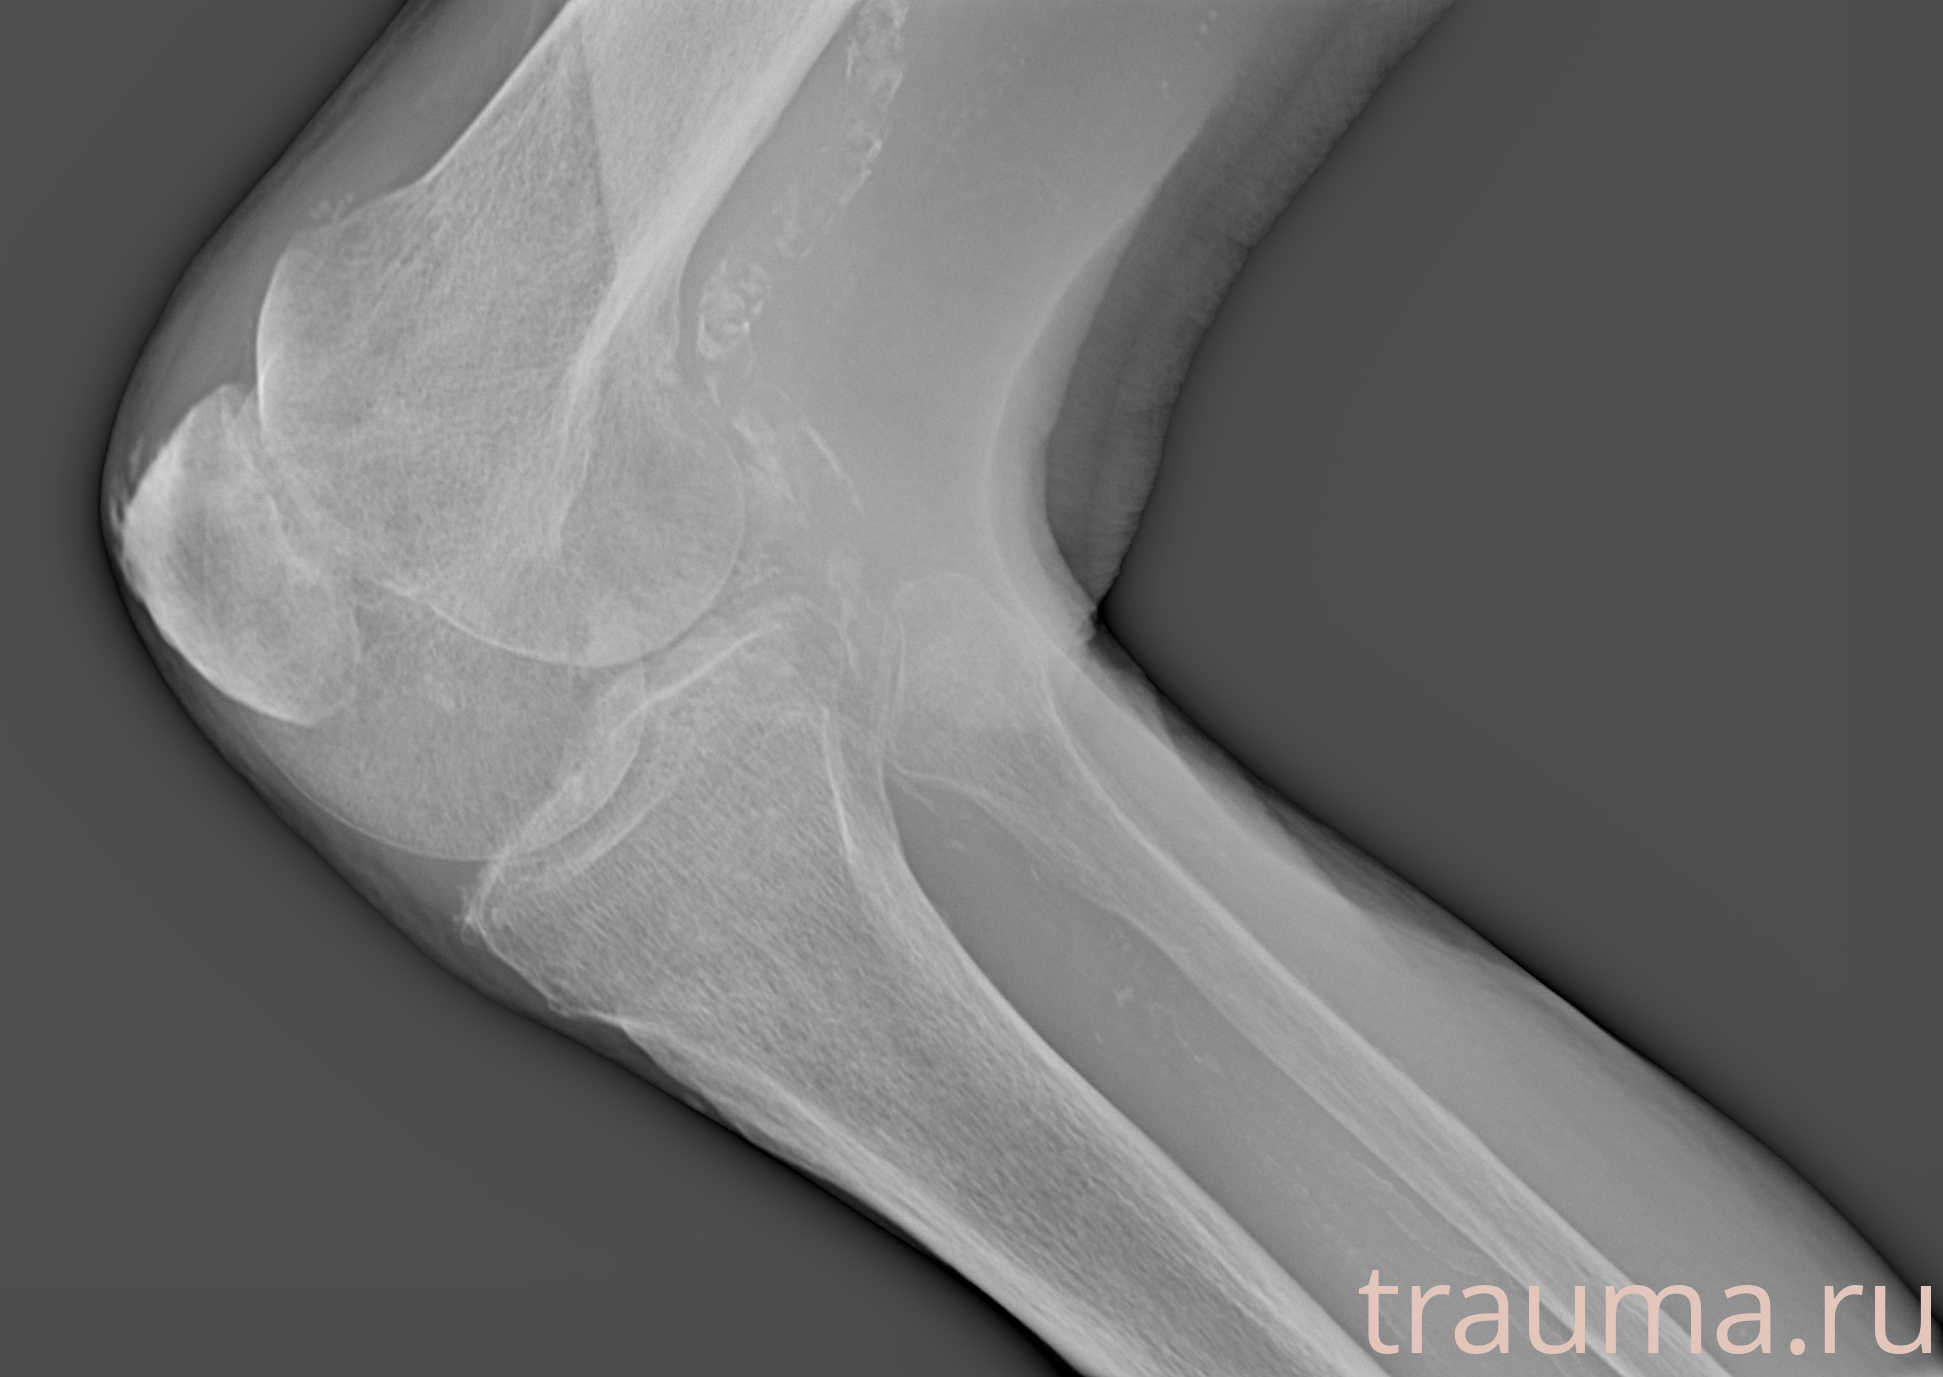

Рентгенограммы

Рентген на дому: по вашему адресу приезжает врач-рентгенолог, травматолог-ортопед с мобильным рентгеновским аппаратом, проводит диагностику травмы или заболевания, делает необходимые рентгенограммы, дает рекомендации по дальнейшему лечению. Получить качественные снимки в домашних условиях возможно благодаря уникальной методике, разработанной МосРентген Центром для института  Склифосовского